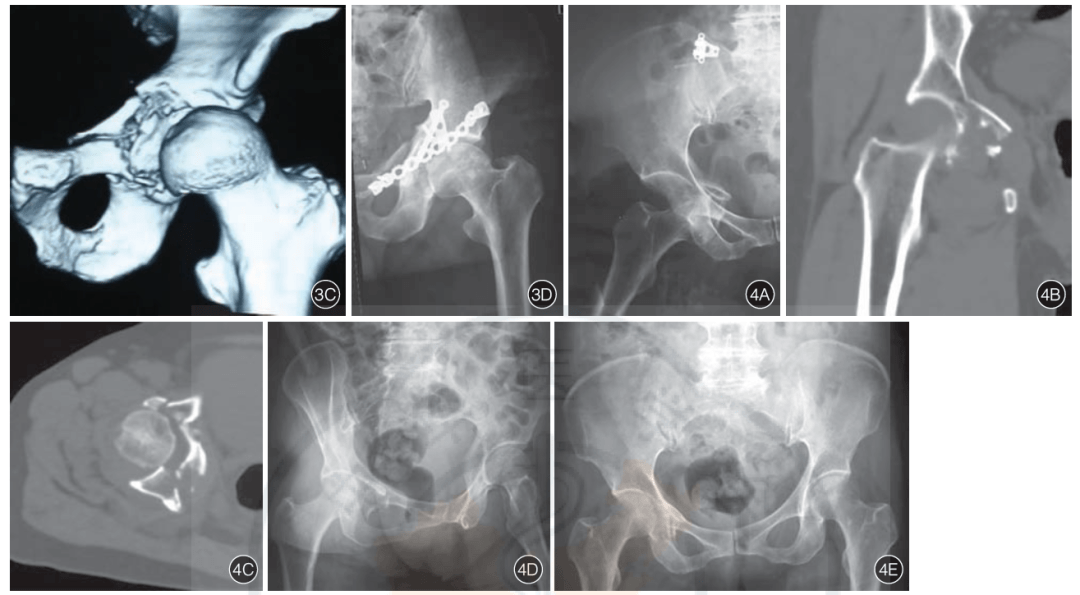

髋臼骨折合并髋关节前脱位的分型及治疗

髋臼前后住骨折伴股骨头中心性脱位